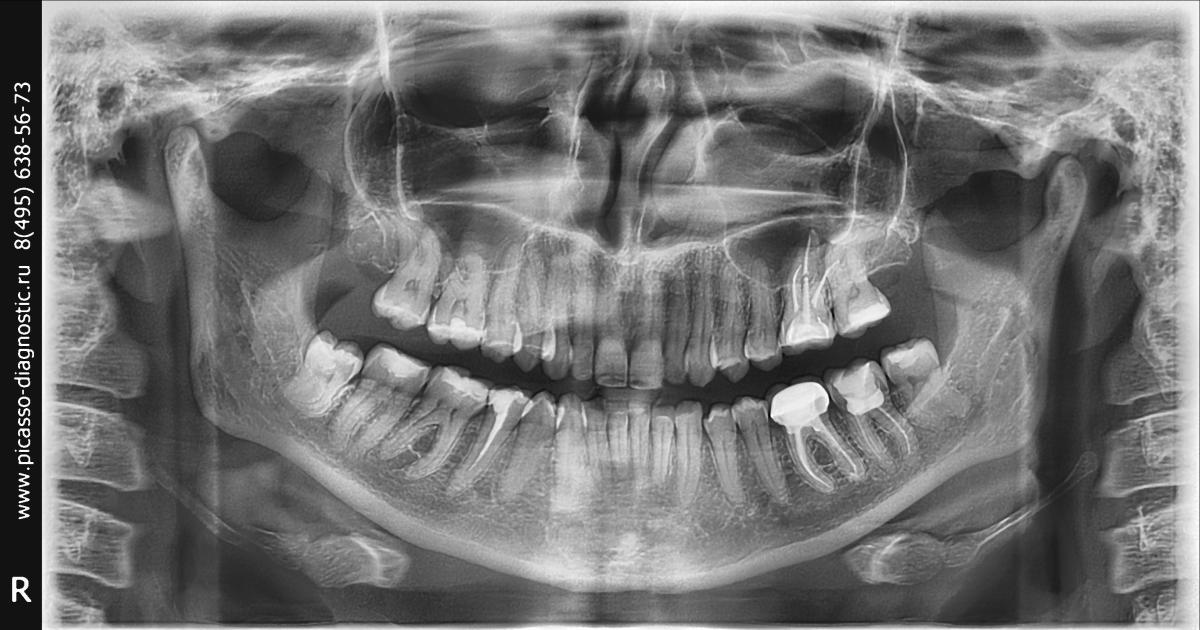

Доьрый день. Подскажите нужно ли ставит коронки на зубы с удаленным нервом? Пришла к стоматологу- ортопеду, у меня 3 зуба стоя без коронок, с удаленным нервом. Сказал необходимо ставить коронки, перед этим перелечить каналы у 5 и 7 ( чем сейчас и занимаюсь). Но уже 100 раз пожалела что начала это все, стояли зубы, они никак не беспокоили, пошла потому что у 5 был не запломбирован канал на половину, но зуб не беспокоил никак. Сейчас в него положили лекарство, он стал серым цветом, хотя до этого был белый. По остальным зубам тоже решила, что раз уж пошла, наверное нужно поставить коронки. Но спросов у многих знакомых, очень у многих стоя зубы без нерва без всяких коронок. Прошу прошение что сумбурно, просо сомнения в правильности того, что сказал стоматолог

Я сторонник покрытия коронками депульпированных зубов.